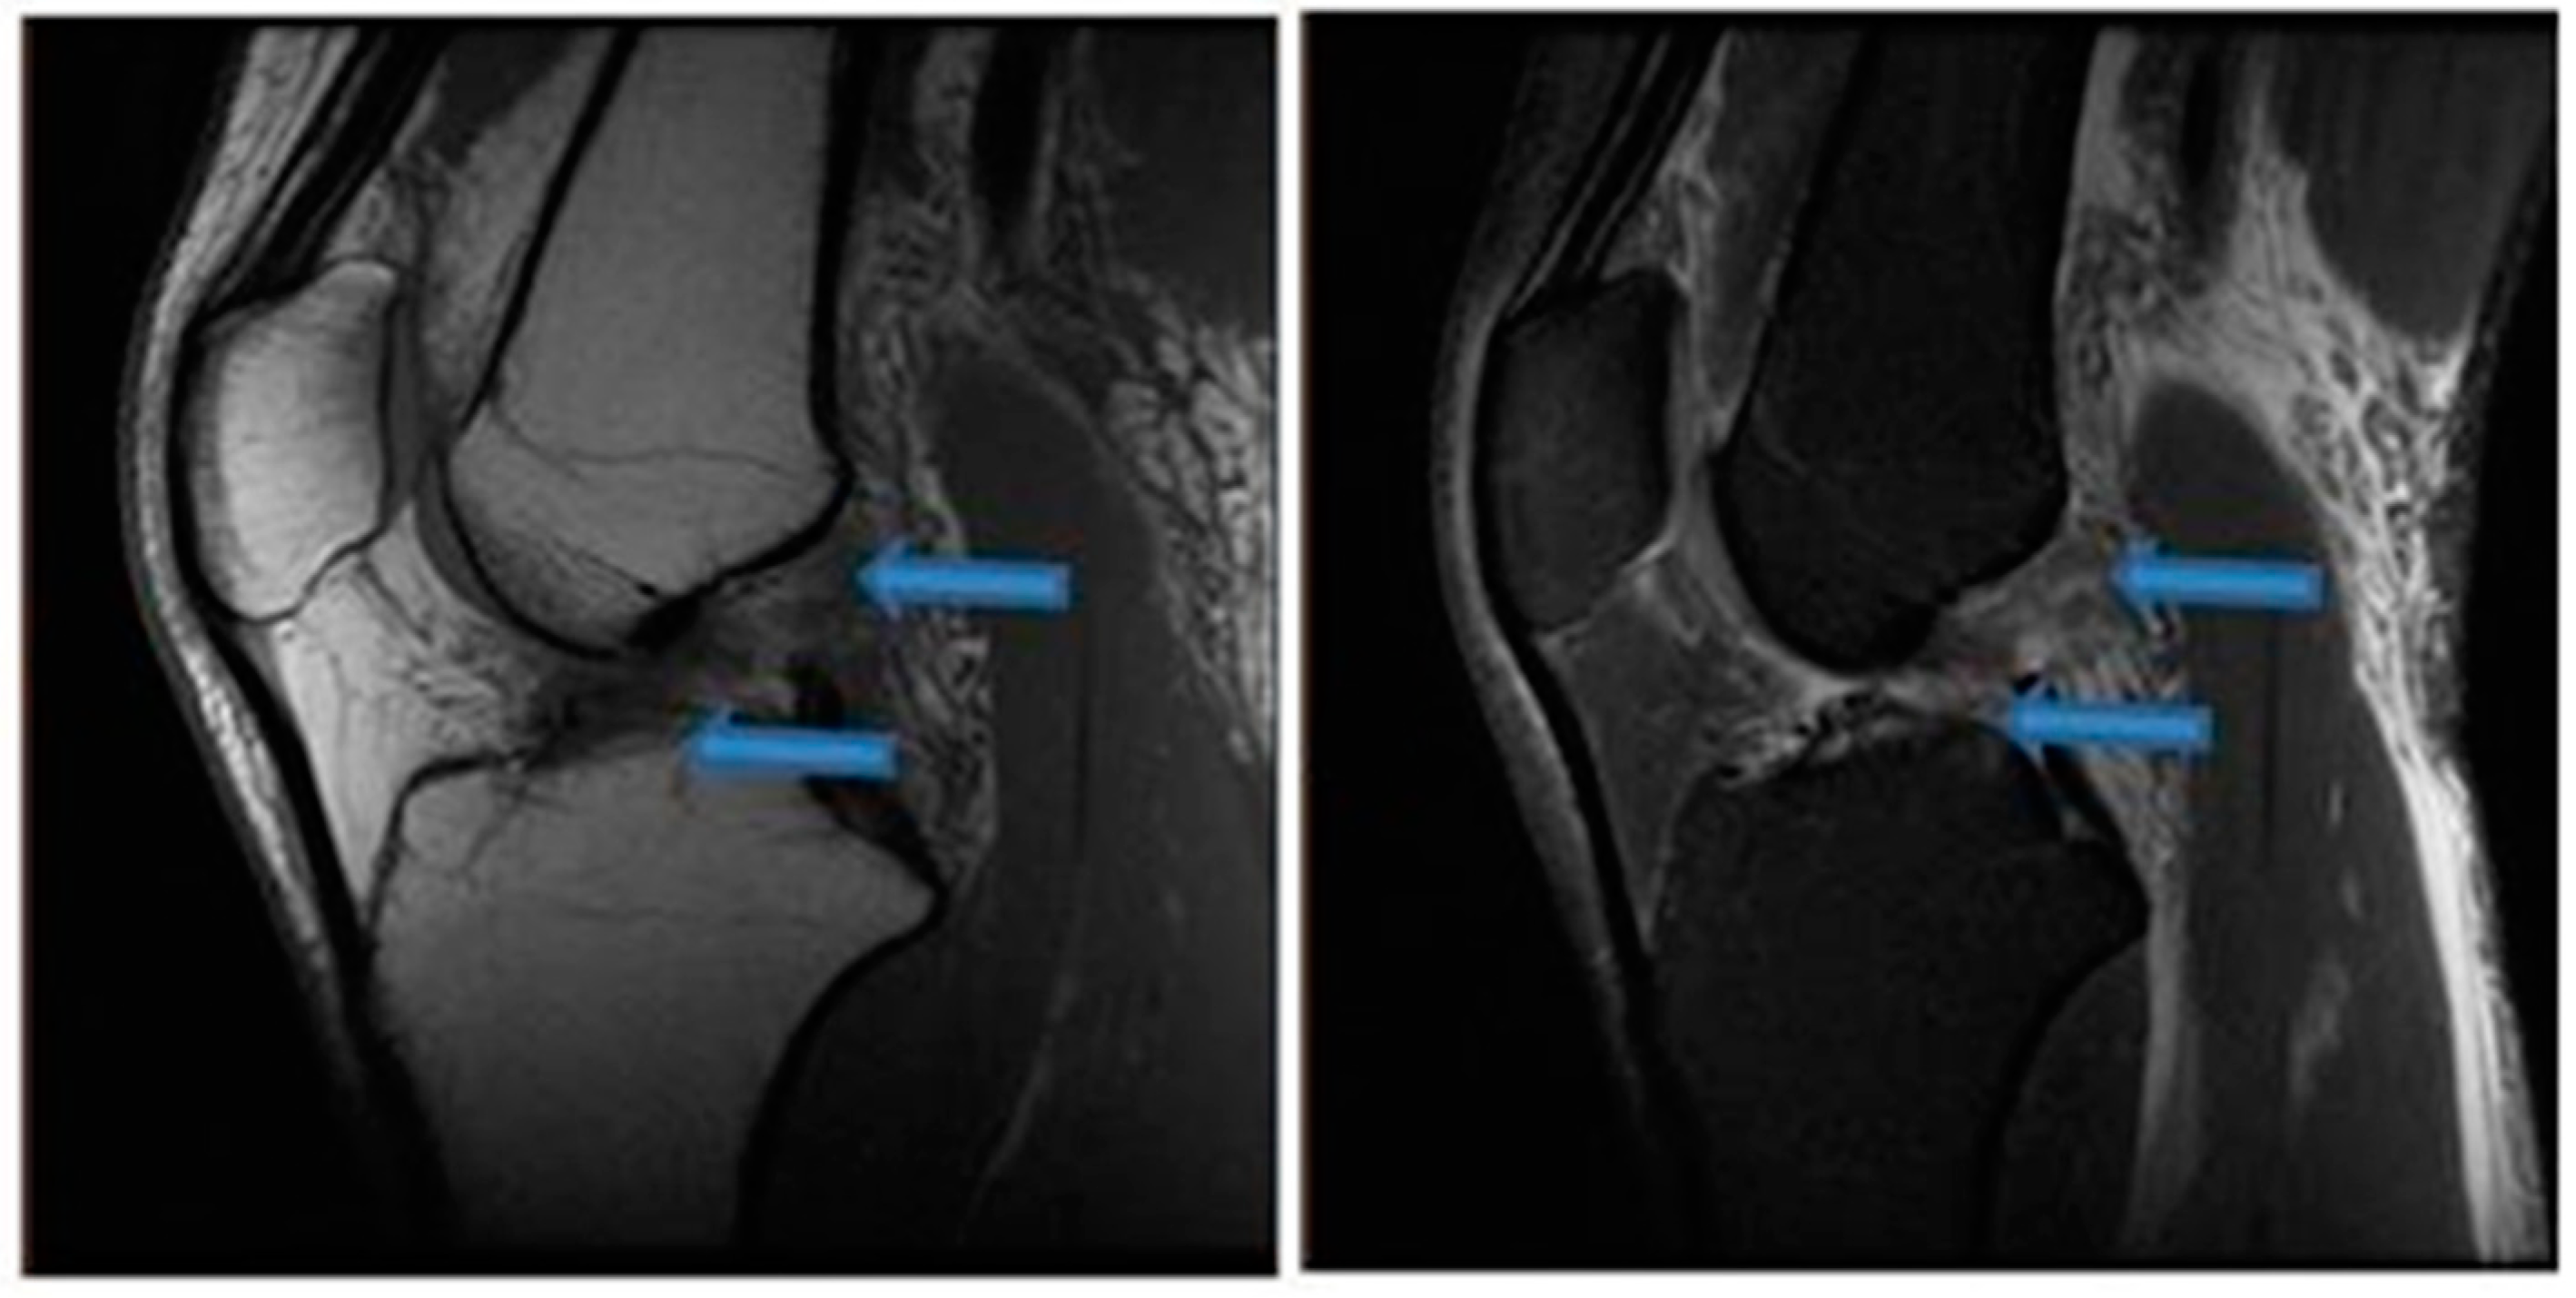

| 9 November 2020 | MRI scans demonstrating signs of partial ACL healing |